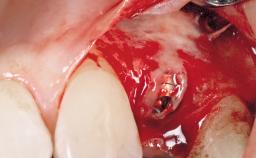

Immediate Flapless Placement of an Implant in a Maxillary Right Lateral Incisor Site

This 43-year-old male patient, a non-smoker, came to our practice because of a fracture of tooth 12 caused by a bicycle accident. Due to the combined para- and infrabony crown and root fracture, tooth extraction, and subsequent implant placement were suggested to the patient as the therapy of choice. The patient had high esthetic expectations with regard to the treatment outcome and asked for an immediate fixed provisional restoration. His individual esthetic risk profile summed up to a medium esthetic risk.

| Placement Protocol | Immediate implant placement |

| Socket Morphology | Single-root socket |

| Socket Integrity | Sufficient, with intact bone walls |